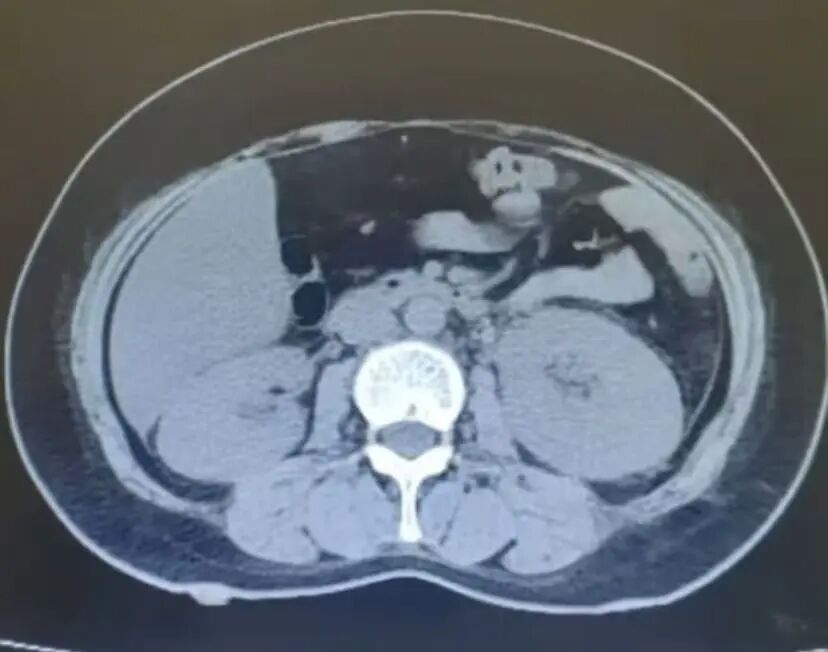

腹部CT显示左肾增大,

左侧输尿管增厚模糊,

周围有渗出改变,

考虑为炎性改变。

腹部CT影像